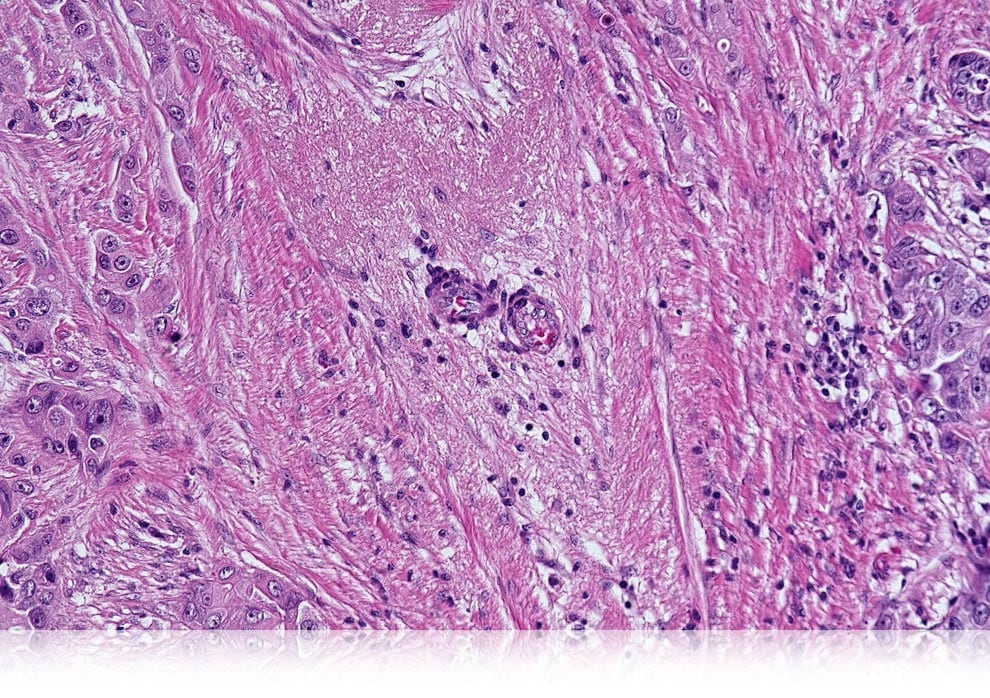

画像連結による遅筋線維比率の定量化

| 筋線維 | 2640 |

|---|---|

| 遅筋線維 | 540 |

| 遅筋線維比率 | 20.5% |

ご提供/東京慈恵会医科大学 分子生理学講座体力医学研究室 山内秀樹 講師